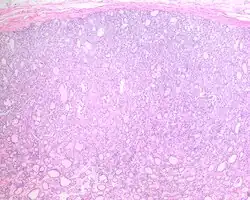

1) Encapsulated or partially encapsulated. The tumors are usually very well delimited or circumscribed, with the majority encapsulated, surrounded by a well formed fibrous connective tissue capsule.

2) Complete absence of invasion of any kind in a tumor that has been thoroughly and carefully evaluated with the whole capsule of the lesion sampled.

3) Predominantly follicular pattern of growth. Papillary structures should not be present. Further, solid, insular, or trabecular architecture must be <30% of the overall tumor for this category to still apply. Colloid (the material that thyroid follicular cells create) is easily identified throughout.